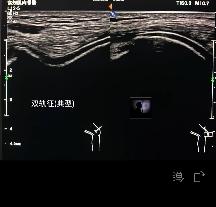

我想多了。医生不仅认真检查了颈椎,还检查了我的肩部、前胸和后背。医生写出超声检测结论后,没有半点敷衍,详细讲解了体位失衡、交感神经等问题,并给出建议:避免多余或不当治疗,先自己进行康复锻炼,配合服用维生素D3。